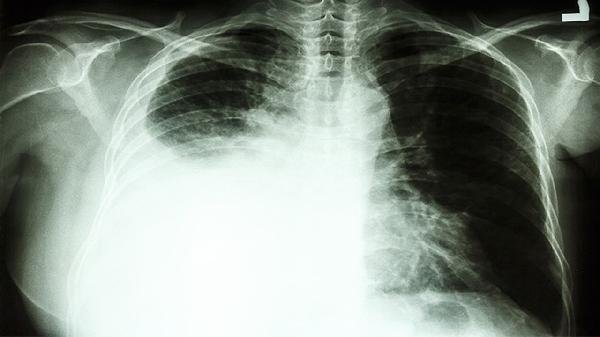

肺癌第一次化疗后身体会有哪些反应

肺癌第一次化疗后可能出现恶心呕吐、骨髓抑制、脱发、疲劳乏力、黏膜炎等反应。化疗药物在杀灭癌细胞的同时也会损伤正常细胞,导致一系列不良反应,多数症状可通过规范处理缓解。